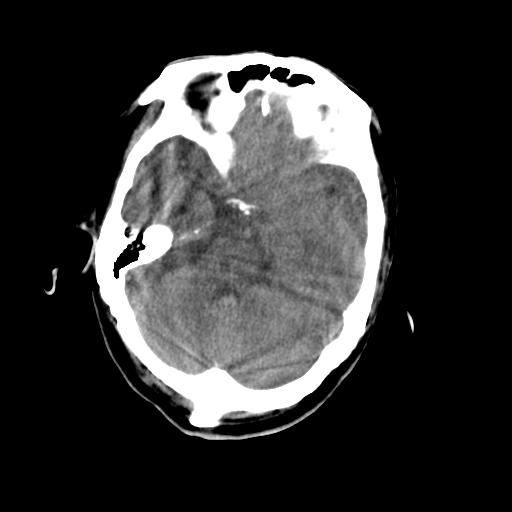

男,78岁。自诉两周前因右侧肢体障碍行ct检查,诊断为脑梗塞(患者ct片已丢失)治疗好转后出院。现因意不清12小时,又行ct检查。

结合病史考虑左侧额颞顶叶出血性脑梗塞。

结合病史考虑左侧额颞顶叶出血性脑梗塞